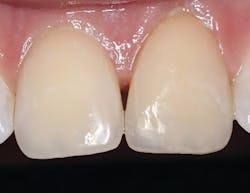

A 28-year-old male fractured the mesial-incisal of tooth no. 9 in a sporting event (figure 5). The tooth was asymptomatic, and no anesthesia was necessary. A 2–3 mm irregular-shaped bevel was prepared using a very fine diamond (45u) with an emphasis on a heavier bevel at the fracture margins and feathering to an infinite bevel approach away from the fractured portion. This not only helps to give the composite more surface area to bond to, but it also creates sufficient thickness to hide the fracture line and allow the material to optically blend into the surrounding tooth structure. After isolation with a Mylar strip, a total-etch technique was utilized followed by Tokuyama Universal Bond. Since the incisal fracture possessed both dentinal shading and a highly translucent enamel component, a two-step approach was implemented for the restorative phase. An increment of the Omnichroma resin was expressed and shaped to mimic the dentinal mamelon effect, and then cured for 20 seconds from the labial and lingual with an LED light. A layer of a translucent composite (Estelite Omega Trans, Tokuyama Dental America) was placed over the cured Omnichroma to give the desired enamel result. After light-curing, interproximal finishing was obtained with a composite strip system (ContacEZ), and occlusion was verified. Shaping was accomplished with the 12 fluted carbides and polished with the abrasive cup and points (figure 6).About the Author